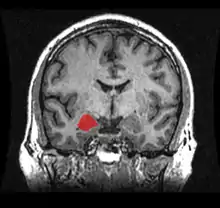

Coronal section of brain through intermediate mass of third ventricle. Amygdala is shown in purple.